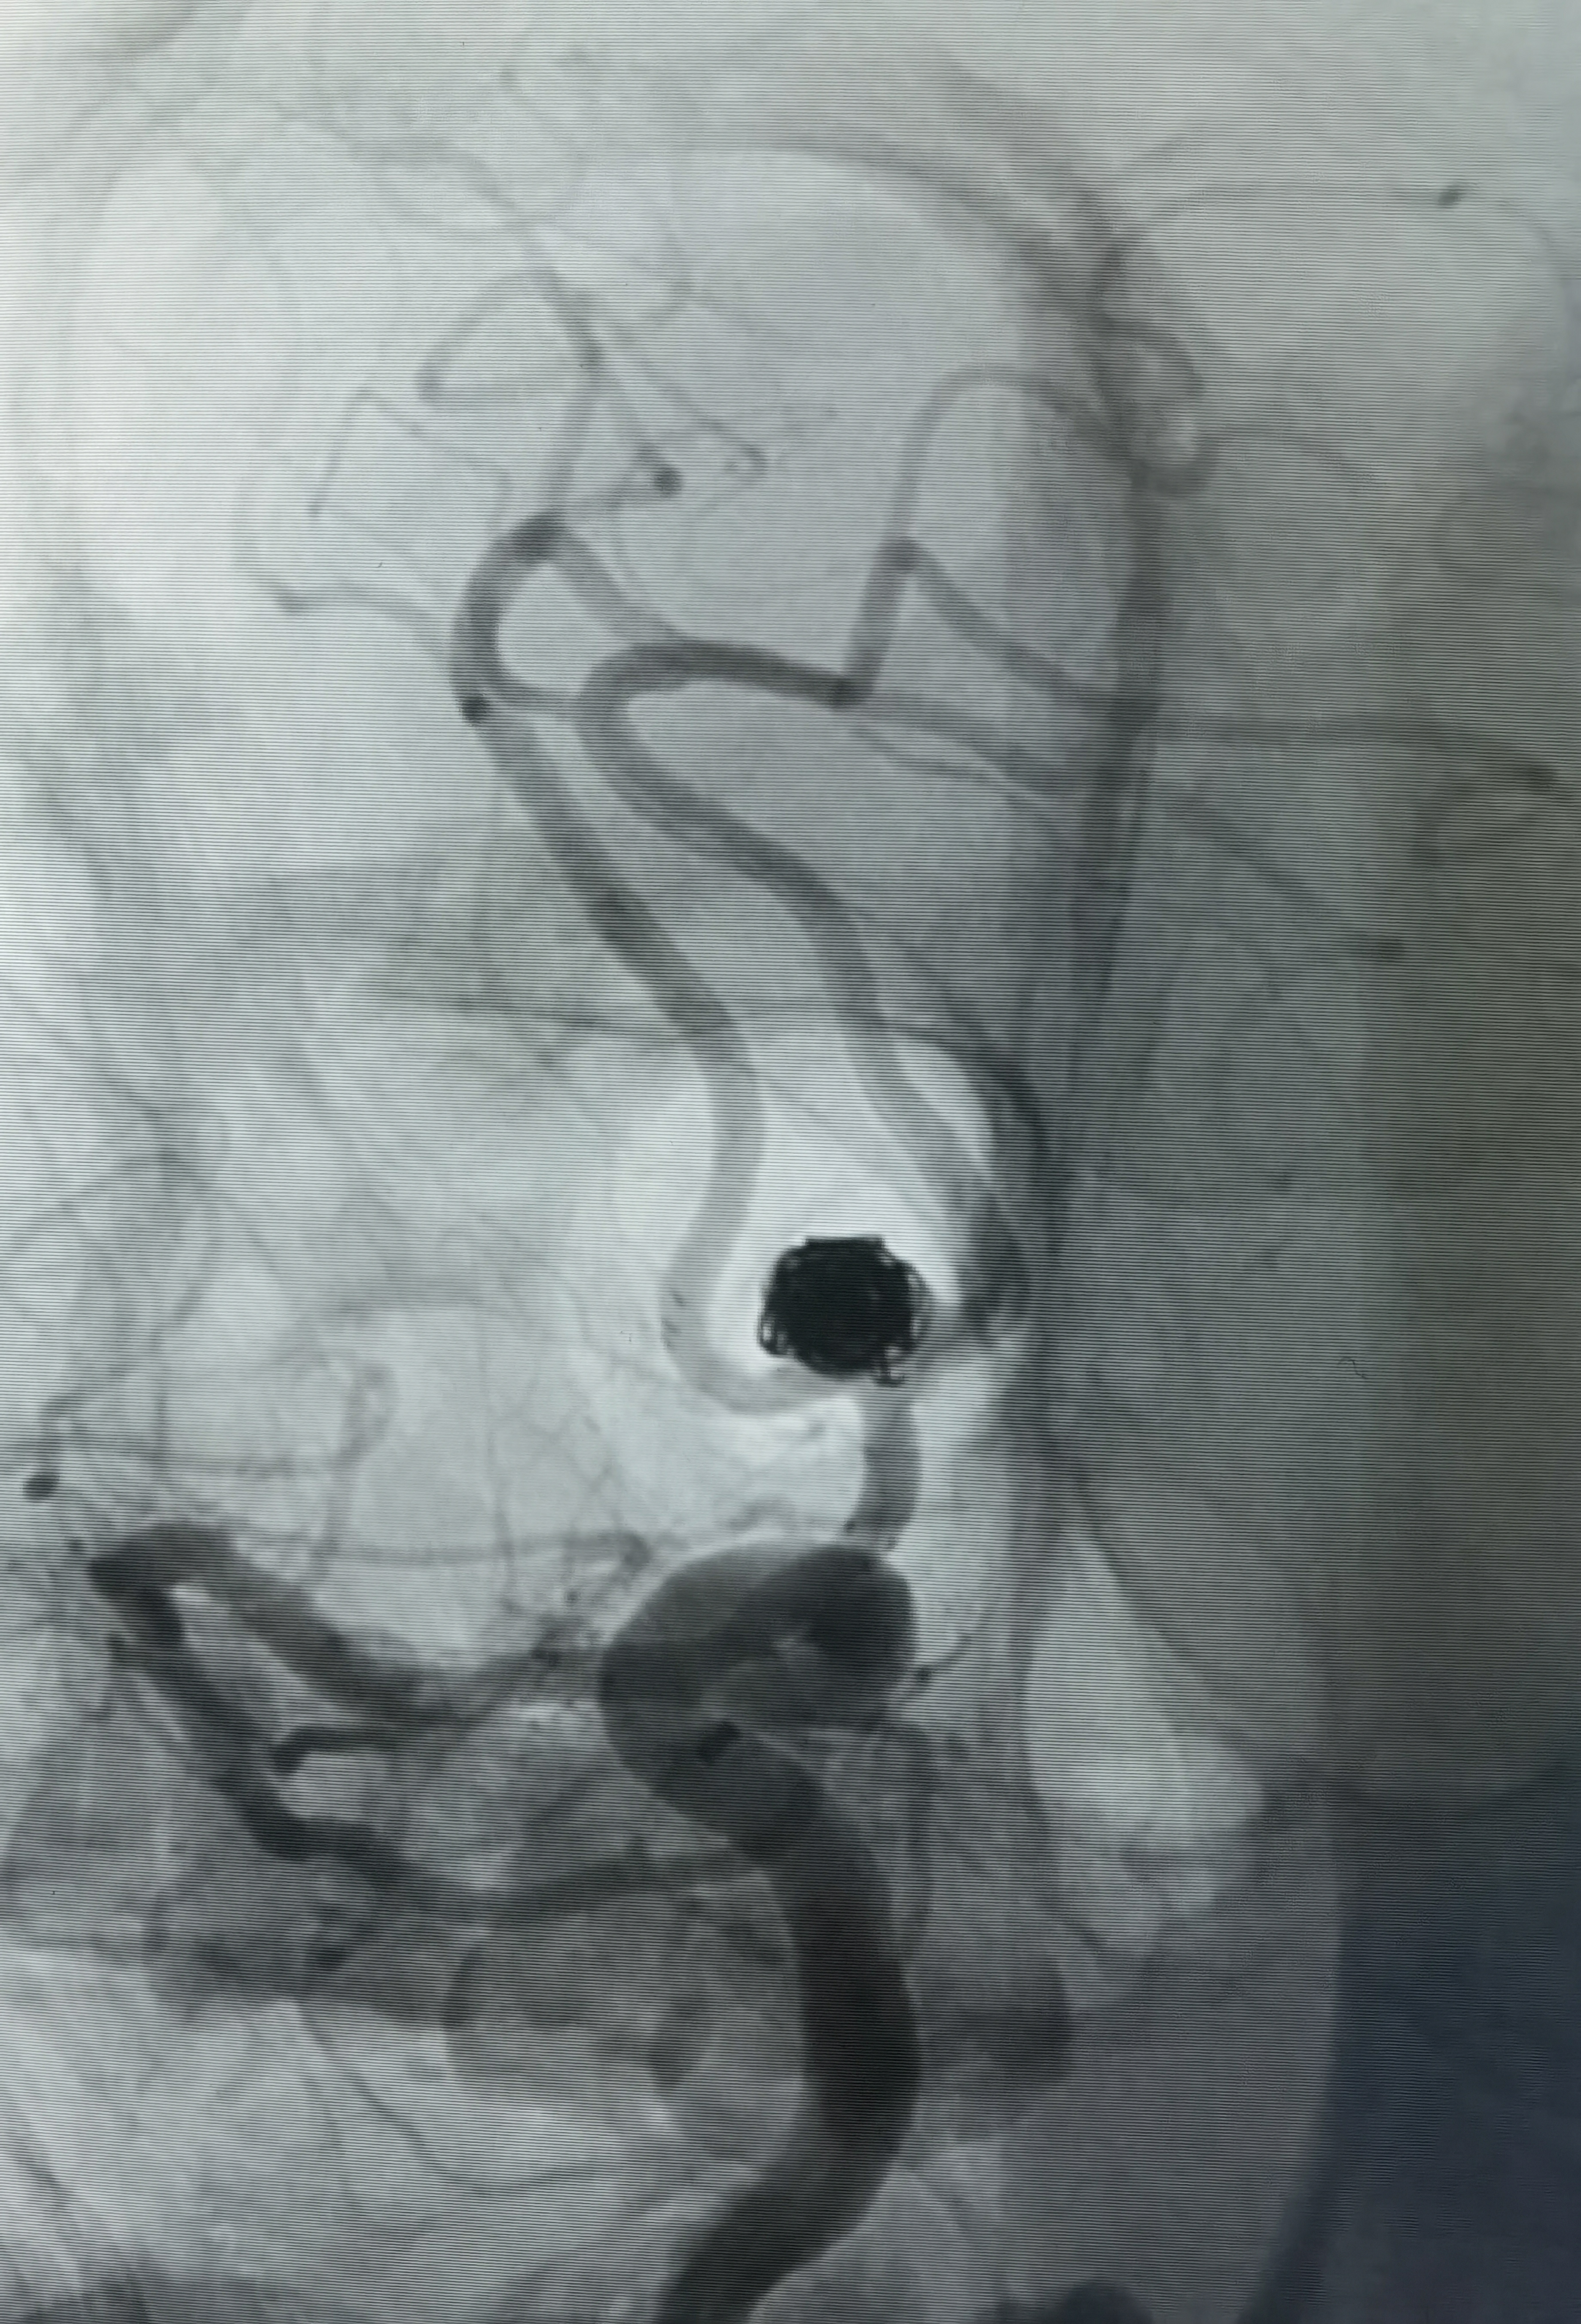

三维旋转造影